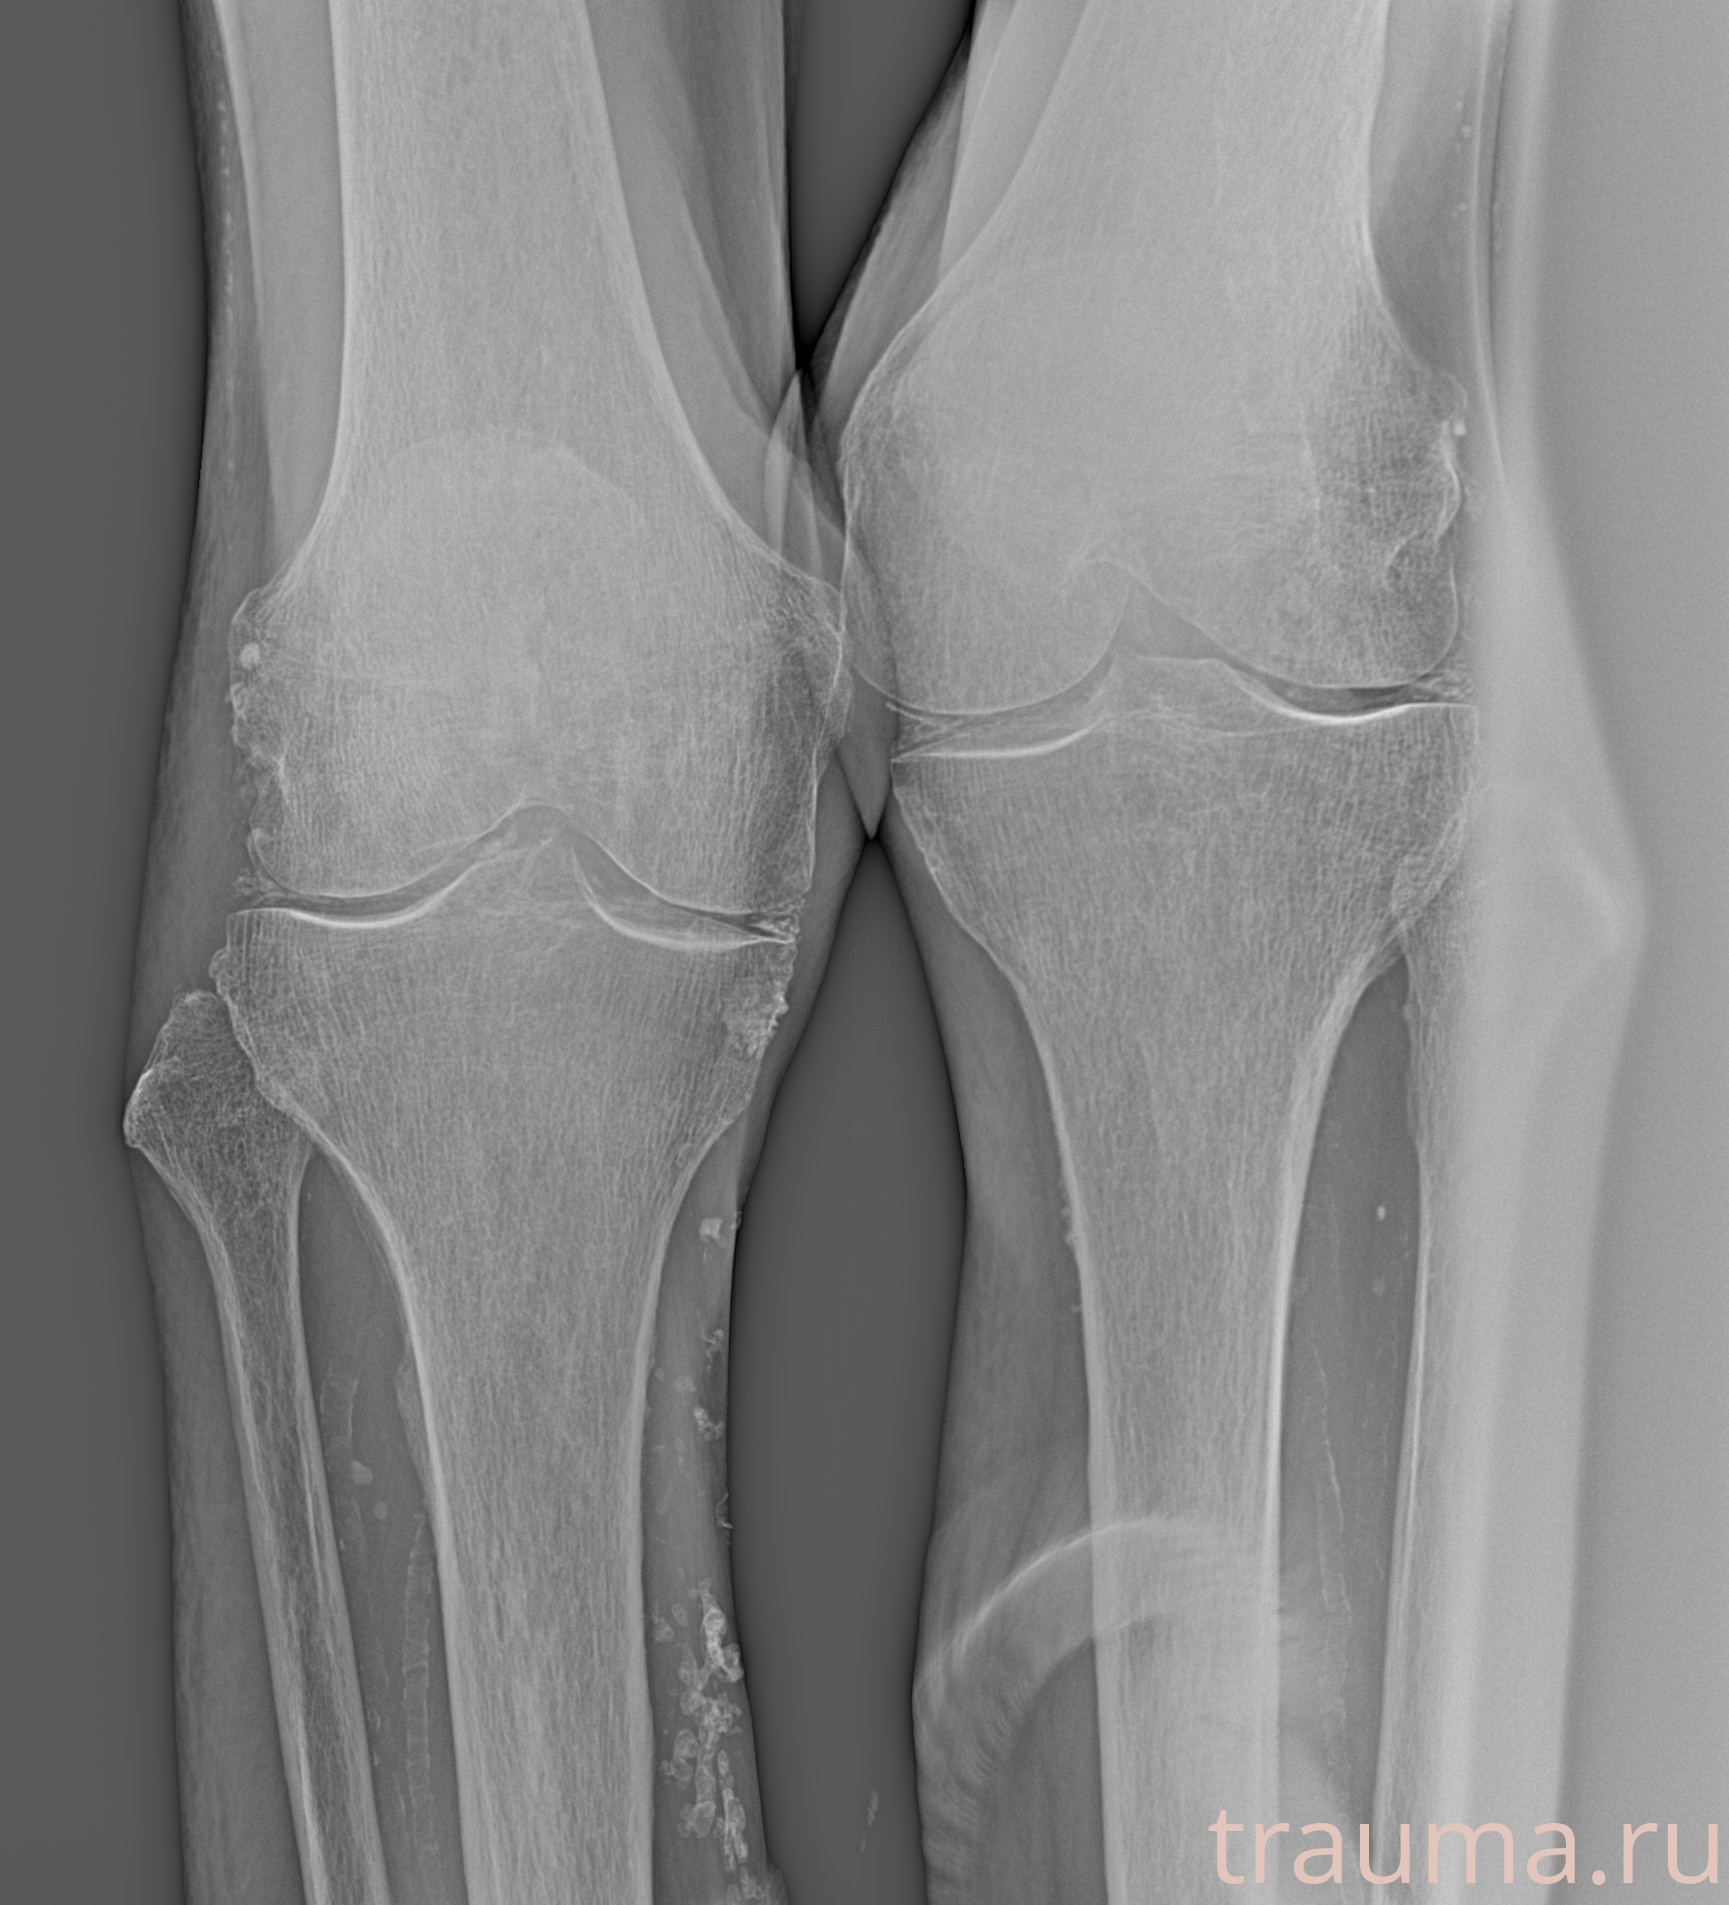

Рентген на дому: по вашему адресу приезжает врач-рентгенолог, травматолог-ортопед с мобильным рентгеновским аппаратом, проводит диагностику травмы или заболевания, делает необходимые рентгенограммы, дает рекомендации по дальнейшему лечению. Получить качественные снимки в домашних условиях возможно благодаря уникальной методике, разработанной МосРентген Центром для института  Склифосовского